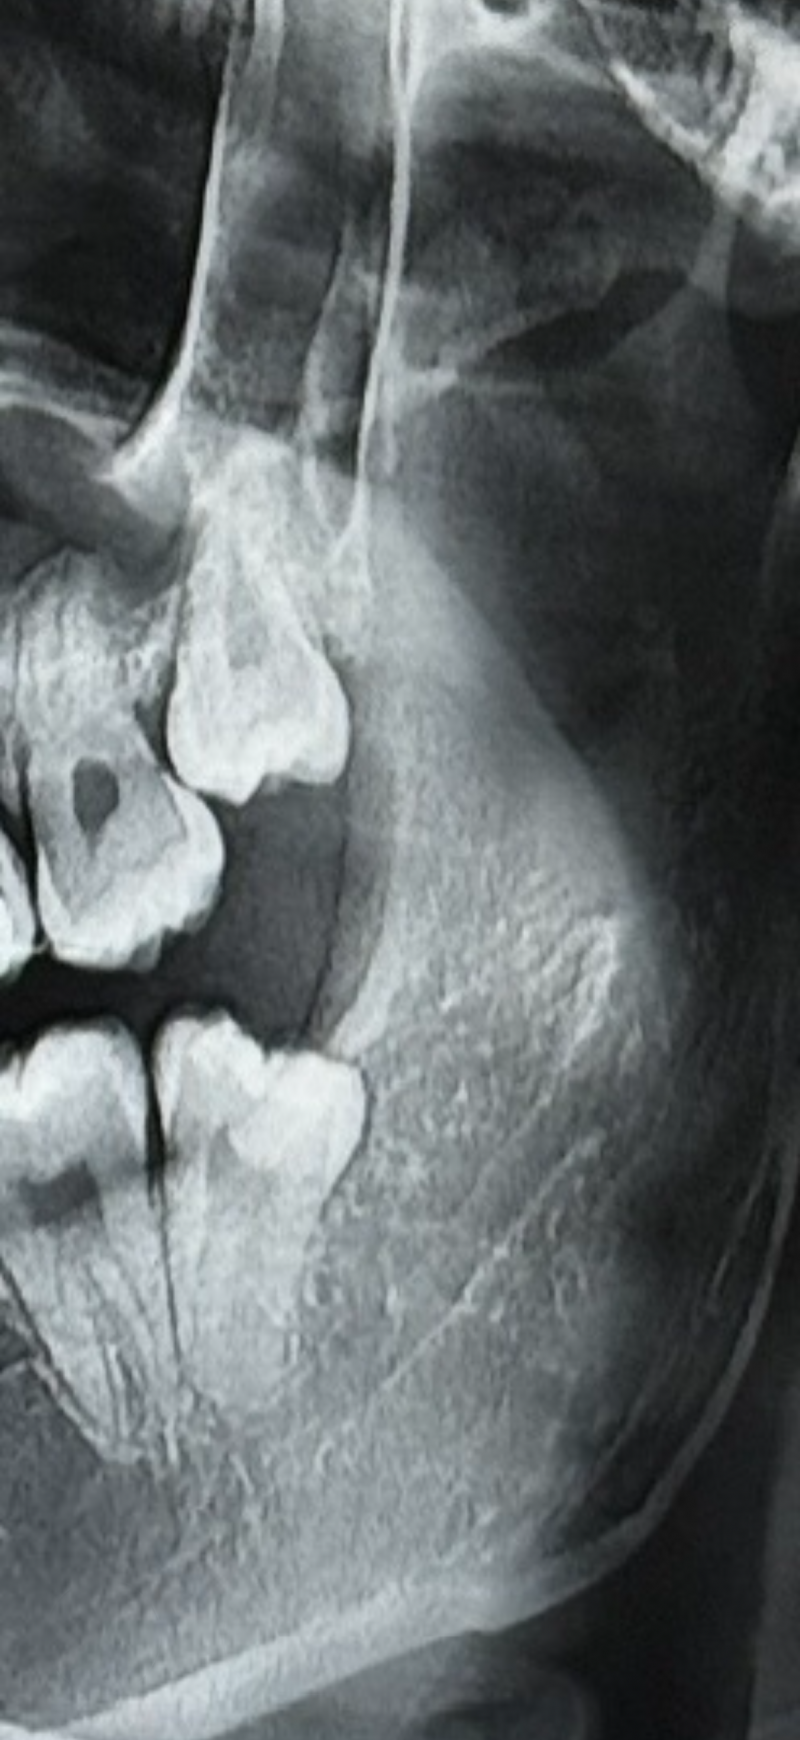

사랑니 잘알있어? 난이도 높은거야?

매복 저정도는 무난

개쉬움

잘하는 곳 가면 하나에 1-2분 컷 함 마취시간 빼고

동네치과에서 빠꾸 먹고 대학병원가라는데 대학병원까지 가야하나해서 ..

동네치과는 당연히 에바고 ㅣㅋㅋㅋㅋ 걍 근처 구강악안면외과 가면 돼 대병도 에바임

신경이랑 엄청 가까운 편도 아니어스

나랑똑같네 그냥뺐어! 아프지도 않았옹